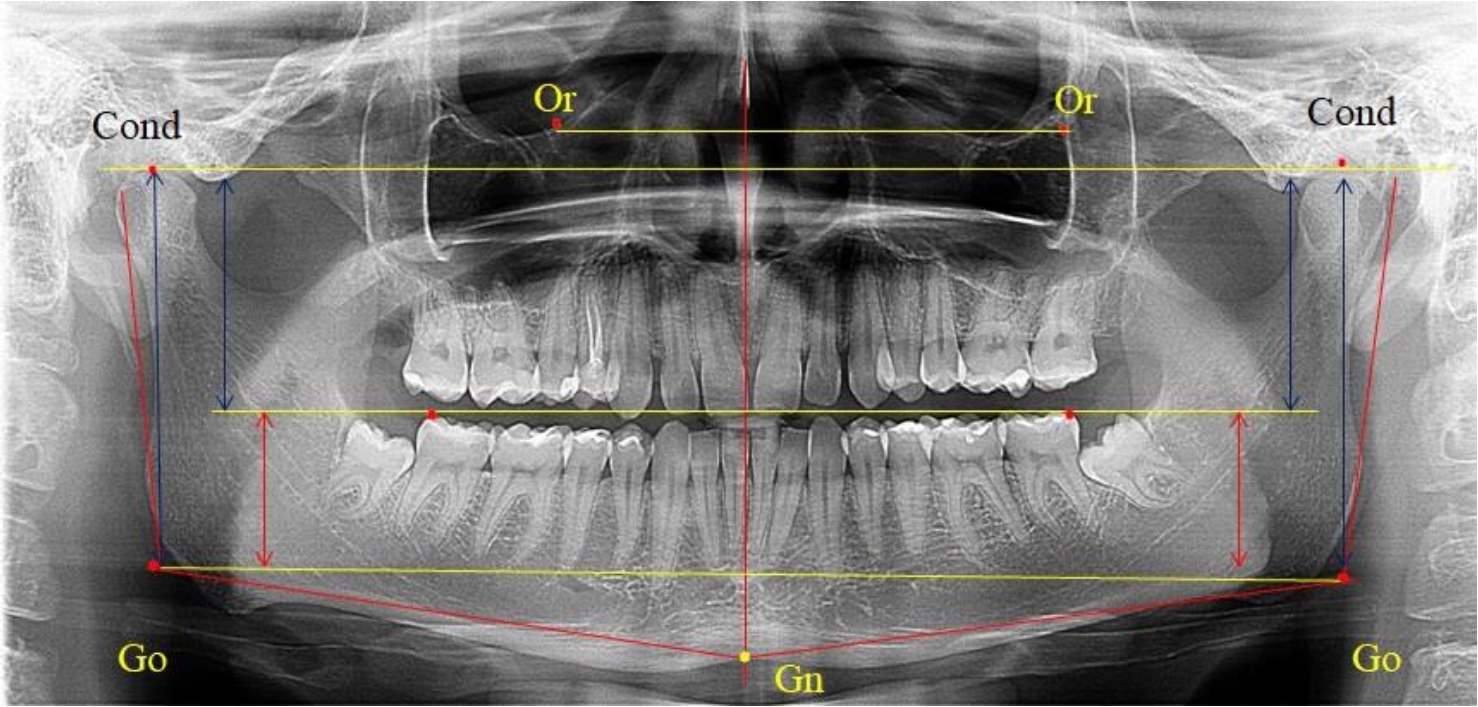

На боковых телерентгенограммах определяли положение верхней точки суставной головки Cond. Касательные линии к ветви и телу нижней челюсти пересекались в точке, которую в клинической практике обозначают как точка угла нижней челюсти или точка гонион Go. Точкой hPOcP обозначали дистальный бугорок нижнего второго моляра вблизи окклюзионного контура коронки, через нее от межрезцовой точки проводили окклюзионную линию, ее продолжали до задней части ветви челюсти. Высоту ветви измеряли как расстояние от угла нижней челюсти до вершины суставной головки Go-Cond. Общую высоту ветви условно делили на 2 части, ее границей служила окклюзионная линия. Верхнюю часть обозначали как окклюзионно-суставная, а нижнюю – как окклюзионно-гониональная.

На ортопантомограмме использовали аналогичные суставные точки Cond на каждой стороне, их соединяли между собой суставной линией Cond-Cond.

Касательная к ветви нижней челюсти соединяла выступающие точку. При построении касательной к телу челюсти проводили в обе стороны линии от точки Gn, расположенной в нижней центральной части подбородочного симфиза, до выступающей нижней точки угла челюсти. Касательные линии при пересечении определяли конструктивную точку гонион Go. Соединение гониональных точек определяло положение гониональной линии Go-Go. При соединении окклюзионных точек hPOcP получали окклюзионную горизонталь (рис. 1). Измеряли расстояние между горизонталями в области ветвей нижней челюсти. Статистический анализ проводили в программе Microsoft Excel. Составляли вариационные ряды с последующим расчетом среднего значения, стандартного отклонения и ошибки среднего ±m. Также оценивали максимальные и минимальные значения величин. Определи относительные величины соотношения верхней и нижней частей ветви нижней челюсти.

Рис. 1. Метод измерения высоты ветви нижней челюсти на телерентгенограмме (а) и ортопантомограмме (б)

3-я подгруппа была с наименьшим количеством анализируемого материала, и здесь было проанализировано 17 комплектов рентгенограмм [(22,97 ± 4,89) %], на которых средняя величина отношения верхней части ветви к нижней составляла 2,45 ± 0,04, что было достоверно больше показателя, полученного по группе в среднем, а также в 1-й и 2-й подгруппе. Визуально параметры ветви отличались от других подгрупп. Высота ветви составляла (57,83 ± 0,89) мм, что было несколько меньше, чем в других подгруппах. Максимальная высота была 64 мм, а минимальная – 53 мм. Высота верхней части составляла (41,03 ± 0,59) мм, что было близким по значениям, полученным в других подгруппах и свидетельствовало о меньшей вариабельности указанного параметра. В то же время высота нижнего отдела ветви была (16,83 ± 0,36) мм и показатель отличался в меньшую сторону, по сравнению с аналогичным размеров в других подгруппах (рис. 4).

Рис. 4. ОПТГ пациента 3-й группы с увеличенным коэффициентом соотношения частей ветви нижней челюсти